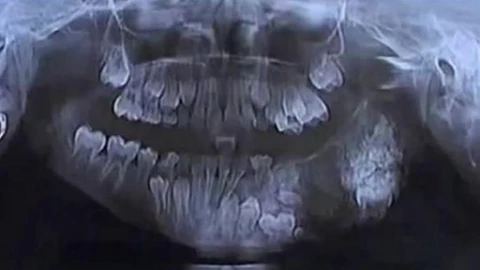

Se dio a conocer el caso de Ravindranath a quien le fueron extraídos 526 dientes de su boca en la ciudad india de Channai.

La operación de extracción duró casi cinco horas y permitió que el pequeño sólo se quedara con 20 dientes, el número que le corresponde a una persona de su edad, con información The Times of India.

La patología se había desarrollado en la parte derecha de la mandíbula desde los tres años y le causaba grandes molestias al menor.

A principios de julio, los médicos le practicaron una radiografía y una tomografía computarizada y le diagnosticaron un odontoma, una condición extremadamente rara. Después de extirparle los 56 dientes extras el pasado 11 de julio, los odontólogos observaron que el tamaño de cada pieza variaba entre un milímetro y un centímetro y medio.

Y todas ellas, incluso la más pequeña, estaban perfectamente formadas y presentaban la corona, la raíz y la capa de esmaltes típicos de cualquier diente sano, destacó la doctora Prathibha Ramani.